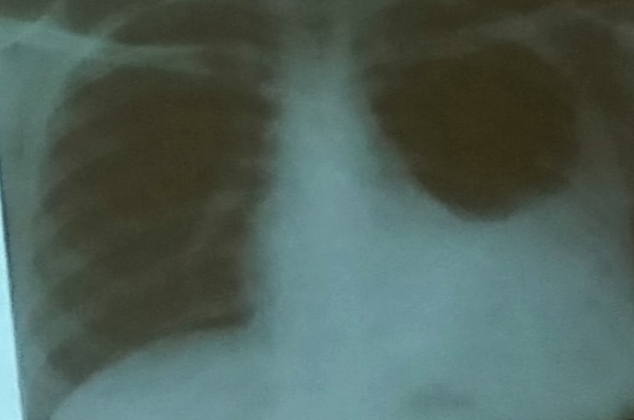

33 year old female presented with malaise, joint discomfort and general feeling unwell. She was diagnosed Graves’ disease four years ago and rendered euthyroid. She had also suffered from celiac disease since her teens. She had no respiratory complaint. She had recent chest X-ray which showed right pleural effusion of moderate size.

Pleural aspiration was performed which showed:

- Pleural fluid sample

- Total protein 33.2 g/l (NR: (1-2 g/dL)

- LDH 287 IU/l (NR: <50% of plasma)

- pH 7.036 (NR: 7.60-7.64)

- Microbiology Nil seen

- Amylase 65U/l

- Rheumatoid factor 557IU/l

Name 2 abnormalities of pleural aspirate? Z a. ---ldh high---

b. ---Protein high--- -

What is the cause of her pleural effusion? Z a. ---Rheumatoid Arthritis---